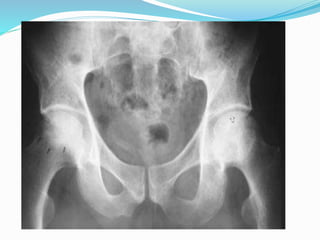

 X-Ray –AP & Frog leg Lat view

I) Stage 1(stage of increased density)

- Ossific nucleus initially smaller; femoral head becomes

uniformly dense;

- Convex rounded enlargement develops at superior margin

of neck( Gage’s sign).

- A subchondral fracture may be seen;

- radiolucencies appear in the metaphysis

II) Stage 2(fragmentation stage)

- Lucency appear in epiphysis;

- Segments (pillars) of the femoral head demarcate the

femoral head may flatten and widen

- Metaphyseal changes resolve;

- Acetabular contour may change